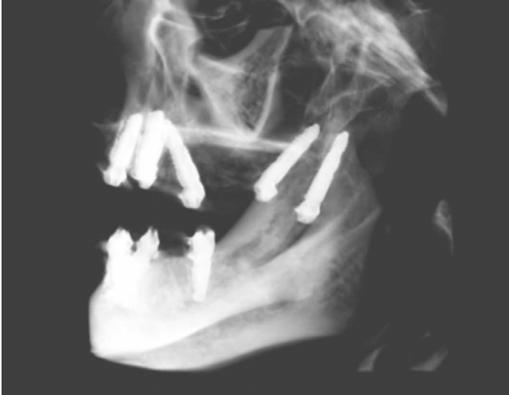

An 80-year-old male with a relatively clean medical history was referred for full-arch immediately loaded maxillary implant treatment. The patient had been previously treated with maxillary dental implants in a traditional All-on-X approach. The referring clinician noted that the patient’s bone was extremely “soft” and that insertion torque for most of the implants was very low. Although these implants were not immediately loaded, they ultimately failed and created large oroantral communications. While the communications were ultimately closed, extremely large

Figure 7 (left): CBCT slice (sagittal view) for vertical measurement from subnasal bone to prelacrimal bone engagement point. Figure 8 (middle): Panoramic radiograph of patient with history of failed All-on-X treatment, oroantral fistulae, and thickened Schneiderian membranes. Figure 9 (right): Intrasurgical photo of transnasal dental implant traversing the nasal cavity and engaging the base of the inferior concha

defects resulted in the floor and walls of the maxillary sinuses (Figure 8). CBCT analysis revealed a significantly thickened left Schneiderian membrane and occluded osteomeatal complex. The patient was referred to ENT for a Functional Endoscopic Sinus Surgery (FESS) procedure. Upon healing, a new CBCT was taken and evaluated for potential treatment.

Due to the atrophic nature of the maxilla, treatment following the PATZi protocol was planned.6,17,20 CBCT evaluation revealed pterygomaxillary bone appropriate for pterygoid implants allowing for posterior arch support and cantilever elimination. The zygomas were of adequate height and width to accommodate multiple zygomatic implant fixtures bilaterally. PLACATE guidelines were used to evaluate the patient for potential treatment with transnasal implants. With Simmen 3 nasolacrimal canal classification, ≥ 3 mm of prelacrimal bone, ≥2 mm subnasal bone, and ≤ 25 mm to the Z-point, the patient satisfied all PLACATE parameters. Accordingly, a treatment plan of bilateral pterygoid, single zygomatic, and transnasal implants was agreed upon.

Following the induction of general anesthesia, extraoral and intraoral local anesthesia was applied. To avoid exposing the large subantral bony defects, mini-flaps were elevated at the pterygoid landing areas to expose the hamular notch. The pterygoid fossa was identified via probing, and pterygoid implant placement ensued. Following the PATZi protocol, bilateral pterygoid implants were placed first and both achieved insertion torque between 45+ Ncm.

Following PATZi, anterior support was sought next. As such, the nasal mucosa was elevated to expose the floor of the nasal cavity and the bone of the inferior conchae. A pair of 25 mm transnasal implants were placed, and each achieved high insertion torque of 45+ Ncm (Figures 9-11). Continuing with the PATZi protocol and treatment plan, 42.5 mm long zygomatic implants were placed in both zygomas. The zygomatic implants were placed using an extrasinus approach and both achieved insertion torque of 45+Ncm. Buccal fat pedicles were advanced bilaterally to cover extrasinus portions of the zygomatic implants, and flap closure was achieved with 4-0 chromic gut suture. The patient was immediately temporized with a screw-retained transitional bridge (Figure 12), and a final zirconia restoration was delivered after 8 months of healing (Figure 13).

Figure 10 (left): CBCT slice (coronal view) of transnasal dental implants engaging the Z-point. Figure 11 (middle): CBCT slice (sagittal view) of transnasal dental implant engaging prelacrimal bone ventral to the nasolacrimal duct. Figure 12 (right): 3-dimensional CBCT rendering of patient treated with transnasal, zygomatic, and pterygoid dental implants via the PATZi protocol

Figure 13: Panoramic radiograph of patient with final zirconia restoration